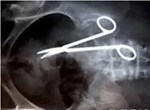

Chiều 4.11, ông Nguyễn Thành Quân, chồng sản phụ bị "kẹt" kim khâu trong bụng Trương Thị Kim Huệ cho biết gia đình đã chấp nhận lời xin lỗi của đại diện Ban giám đốc Bệnh viện đa khoa tỉnh Ninh Thuận.

Bên cạnh đó, bệnh viện sẽ chịu mọi chi phí cho ca phẫu thuật sau này để lấy đầu kim khâu trong vùng tiểu cung của sản phụ Huệ.

Như đã đưa tin, sản phụ Huệ nhập viện chiều 29.10, được chẩn đoán thai 40 tuần chuyển dạ, ngôi đầu. Do vết mổ cũ của sản phụ gây đau nên khi chuyển dạ bác sĩ chỉ định mổ lấy thai.

Sau khi đưa thai nhi ra khỏi bụng mẹ an toàn, bác sĩ tiến hành khâu phủ phúc mạc thì kim khâu bị gãy, nên tiến hành chụp X-quang tại phòng mổ và phát hiện dị vật (đầu kim) ở vùng tiểu cung.

Sau đó, các bác sĩ đã hội chẩn nhưng vẫn không tìm thấy nên quyết định đóng ổ bụng.

Lãnh đạo Bệnh viện đa khoa Ninh Thuận cho biết, đây là sự cố ngoài ý muốn, bệnh viện đã tham khảo ý kiến chuyên môn của tuyến trên và được hướng dẫn sau 6 tuần sẽ phẫu thuật lại để lấy dị vật.